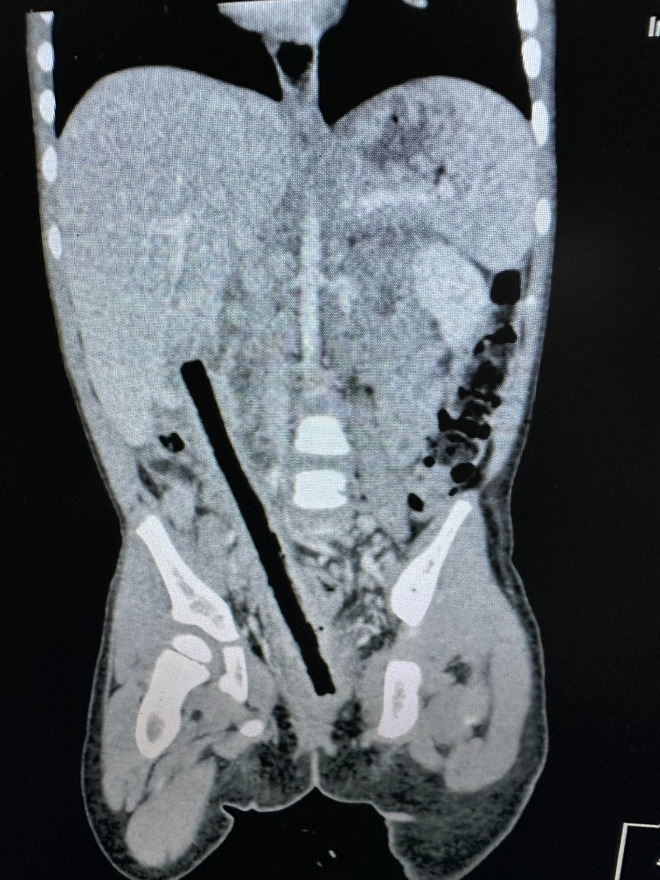

Theo BSCK1 Nguyễn Hiền, Khoa Ngoại tổng hợp - Bệnh viện Nhi Đồng 2, kết quả CT scan cho thấy trong ổ bụng bệnh nhi có dị vật kích thước 1x16 cm nằm vùng từ trực tràng đến gan.

Ê-kíp nội soi xác định dị vật đâm xuyên trực tràng, ruột non và tá tràng viêm dính nhiều, gây khó khăn cho phẫu thuật. Các bác sĩ tiến hành mổ mở bóc tách dọc theo dị vật, tách dính toàn bộ ruột, tránh làm tổn thương các mạch máu thần kinh và niệu quản, hạn chế các tổn thương các bộ phận khác.

Sau 4 giờ phẫu thuật, các bác sĩ đã lấy ra nguyên vẹn nhành cây dài 16 cm. Bệnh nhi được xử lý cầm máu, khâu các vết thương và làm hậu môn tạm. Hiện bé đang dần hồi phục và dự kiến sẽ xuất viện sau 1 tuần.